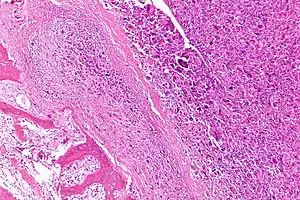

| Intermediate-magnification micrograph of an osteosarcoma (center and right of image) adjacent to non-malignant bone (left-bottom of image): The top-right of the image has poorly differentiated tumor. Osteoid with a high density of malignant cells is seen between the non-malignant bone and poorly differentiated tumor (H&E stain). | |

Microscopically: The characteristic feature of osteosarcoma is presence of osteoid (bone formation) within the tumor. Tumor cells are very pleomorphic (anaplastic), some are giant, numerous atypical mitoses. These cells produce osteoid describing irregular trabeculae (amorphous, eosinophilic/pink) with or without central calcification (hematoxylinophilic/blue, granular)—tumor bone. Tumor cells are included in the osteoid matrix. Depending on the features of the tumor cells present (whether they resemble bone cells, cartilage cells, or fibroblast cells), the tumor can be subclassified. Osteosarcomas may exhibit multinucleated osteoclast-like giant cells.[21]